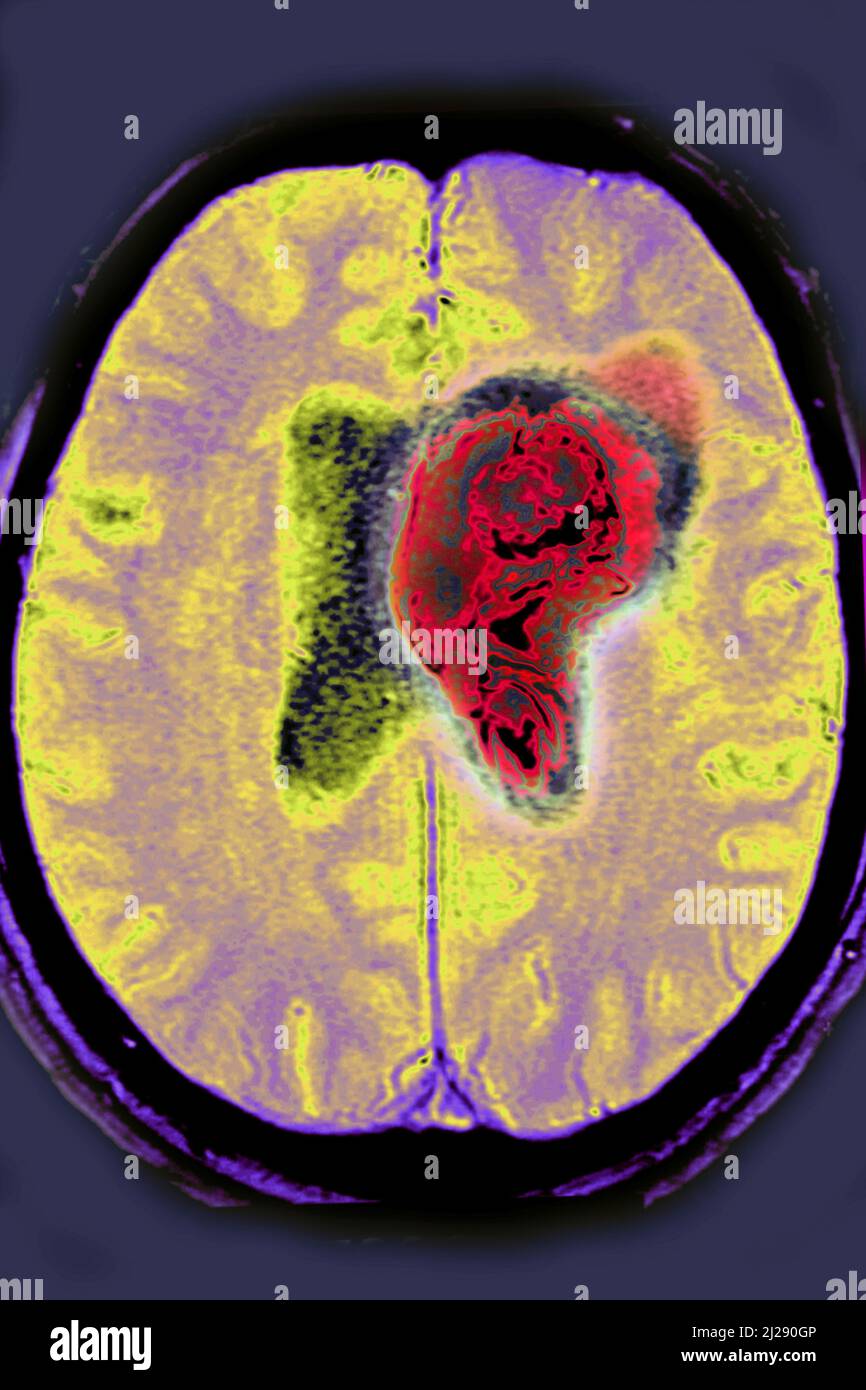

Hemorrhagic stroke is a clinical diagnosis where an acute neurological deficit follows a bleed into the brain parenchyma. Treatment of hemorrhagic stroke focuses on controlling the bleeding and reducing pressure in your brain caused by the excess fluid. Understanding the hemorrhage risks associated with brain arteriovenous malformations (avms) before and after stereotactic radiosurgery. Haematoma expansion, intraventricular haemorrhage, perihaematomal oedema, and inflammation, can all cause an acute. Characteristics of patients and avm related to hemorrhagic or nonhemorrhagic presentation were evaluated by logistic regression. Investigations of the combined effects of neoadjuvant onyx embolization and stereotactic radiosurgery (srs) on brain. Although complete nidal obliteration of brain arteriovenous malformations (avm) is generally presumed to. This is a summary article;

CT scan of brain with red area ( Imaging for hemorrhagic stroke or Radiosurgery Hemorrhagic Stroke Although complete nidal obliteration of brain arteriovenous malformations (avm) is generally presumed to. Understanding the hemorrhage risks associated with brain arteriovenous malformations (avms) before and after stereotactic radiosurgery. Investigations of the combined effects of neoadjuvant onyx embolization and stereotactic radiosurgery (srs) on brain. Haematoma expansion, intraventricular haemorrhage, perihaematomal oedema, and inflammation, can all cause an acute. This is a summary. Radiosurgery Hemorrhagic Stroke.